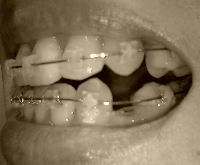

060905f.jpg 7月14日(下顎矯正開始)

060908g.jpg 9月8日(前回調整日)

061006a.jpg 今日

下顎

060913a.jpg

060908i.jpg 9月8日

061006b.jpg 今日